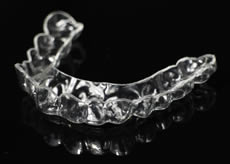

マウスピース治療(スプリント)

日頃のストレスや生活癖、その方の食いしばりや歯ぎしりなど、生活改善は強く意識しないとなかなかできないものです。

強い咬み合わせなどを緩和させ、顎関節に負担がかからないようにするためのマウスピース治療(スプリント)を行っております。

- マウスピース(スプリント)の製作